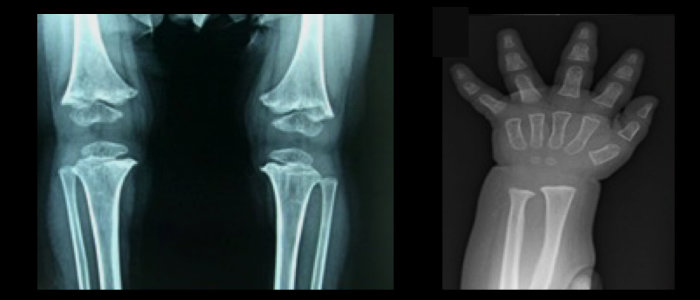

RNA Development & Disease

X-ray images showing a child's knee joint on the left and a child's hand on the right.